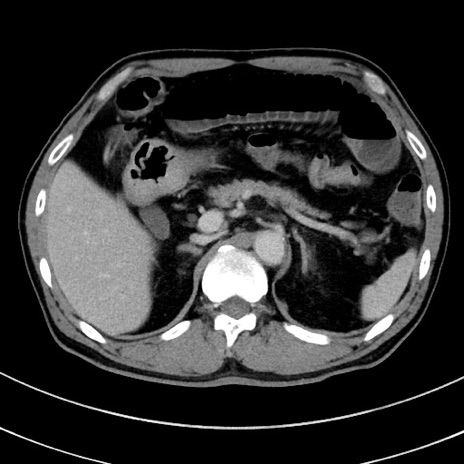

症例8(横断像)

【症例】 60歳代男性

【主訴】 黒色吐物

【現病歴】 4日前から嘔気自覚、2日前の朝食後にも嘔気あり、自分で手で嘔吐反射起こし嘔吐したところ血が混ざっていたため受診。

【既往歴】 5年前汎発性腹膜炎を伴う急性虫垂炎で手術、高血圧、前立腺肥大症、高脂血症

【身体所見】 腹部正中に手術癩痕あり 腹部平坦・軟圧痛なし膨満感あり

【データ】WBC 8400、CRP 4.54